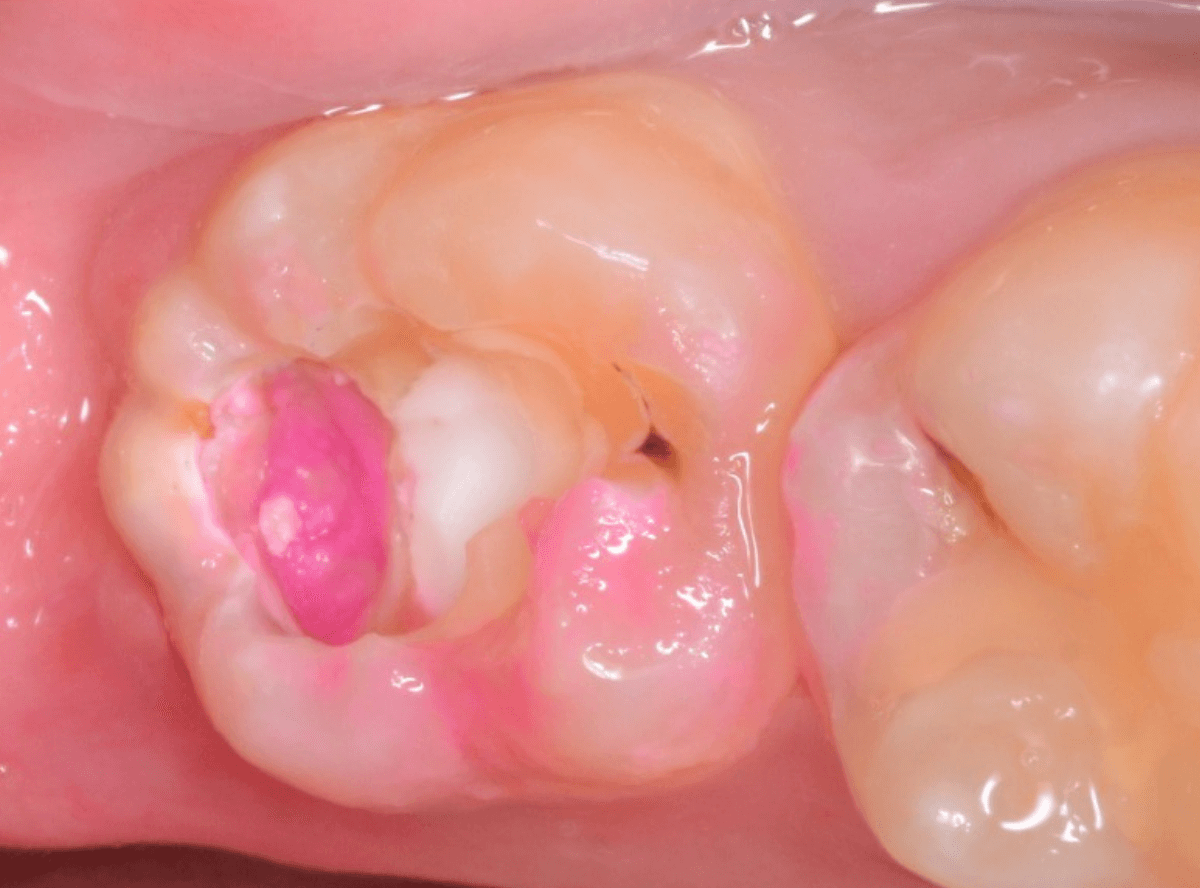

麻酔をして、治療を開始します。

レジンを外すと、中から出血してきました。

これは、歯のスキマに歯肉が入り込んでしまったために起こってしまったものです。

おそらく、随分前から虫歯が進行していたと思われます。

止血しながら、電気メスで歯の中に入り込んだ歯肉を除去します。

虫歯と入り込んだ歯肉でぐちゃぐちゃになっている状態でした。

これでは、痛みが出てもおかしくありません。

慎重に全ての虫歯を除去したところです。

〇部が神経の入り口が見えているところです。

神経を保護する処置をして、しばらく経過観察しますが、痛みが出て神経を除去する必要が出る可能性も高いです。